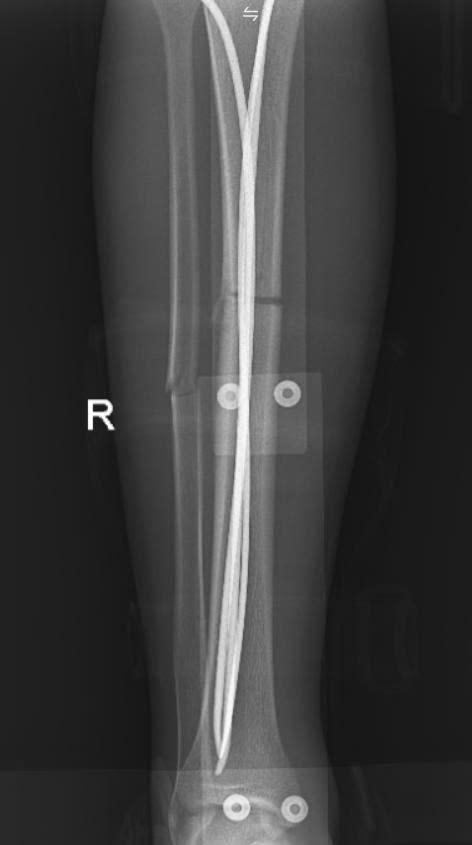

Sau hội chẩn chuyên môn, người bệnh được chỉ định phẫu thuật kết hợp xương dưới hướng dẫn của hệ thống màn hình tăng sáng (C-arm). Đây là thiết bị hiện đại hỗ trợ bác sĩ quan sát rõ vị trí ổ gãy trong suốt quá trình phẫu thuật, giúp nắn chỉnh xương về đúng trục giải phẫu và đặt dụng cụ cố định xương một cách chính xác, hạn chế tối đa sang chấn cho người bệnh.

Ca phẫu thuật được tiến hành ngay trong đêm và diễn ra thuận lợi. Các bác sĩ đã cố định vững chắc ổ gãy, xử trí tốt phần mềm và vết thương hở, tạo điều kiện thuận lợi cho quá trình liền xương và phục hồi chức năng vận động. Sau 6 ngày điều trị, tình trạng người bệnh ổn định và được xuất viện theo đúng dự kiến.